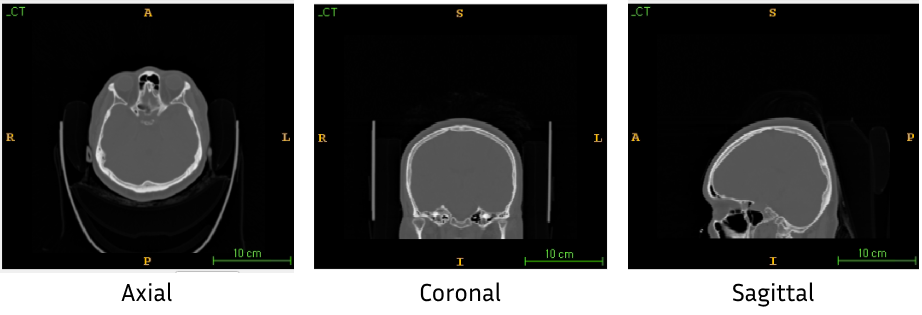

cf) Axial이란?

3D 영상의 수평면을 말한다. 즉, 우리가 흔히 생각하는 z축에 수직인 방향으로 영상을 잘랐을 때 보이는 면을 axial plane이라고 한다. Sagittal과 Coronal 방향도 존재하는데, 이들은 축에 비유하기 보다는 촬영한 환자 기준으로 이해하는 게 편하다. Brain을 촬영했다고 가정했을 때, 머리의 양옆을 지나는 면을 coronal , 앞뒤를 지나는 면을 sagittal이라고 부른다.